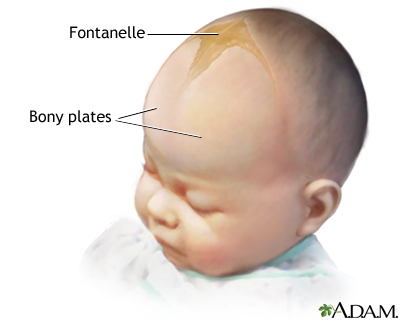

what are fonatelles? why do they exist?

Babies have much wider/expansive sutures: fonatelles

- anterior fontanelle found between two parts of frontal bone.

- this helps with post-natal growth of the skull and allows the brain to grow/expand, and also helps head deformity during birth. Can measure intercranial pressure, will bulge if pressure in skull has increased

what are fonatelles? why do they exist?

Babies have much wider/expansive sutures: fonatelles

- anterior fontanelle found between two parts of frontal bone.

- this helps with post-natal growth of the skull and allows the brain to grow/expand, and also helps head deformity during birth. Can measure intercranial pressure, will bulge if pressure in skull has increased